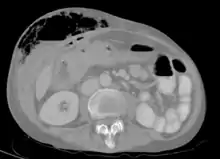

Abdominal CT scan with right colocutaneous fistula and associated subcutaneous pneumatosis

In anatomy, a fistula (pl.: fistulas or fistulae /-li, -l/; from Latin fistula, "tube, pipe") is an abnormal connection (i.e. tube) joining two hollow spaces (technically, two epithelialized surfaces), such as blood vessels, intestines, or other hollow organs to each other, often resulting in an abnormal flow of fluid from one space to the other.[2][3][4] An anal fistula connects the anal canal to the perianal skin. An anovaginal or rectovaginal fistula is a hole joining the anus or rectum to the vagina. A colovaginal fistula joins the space in the colon to that in the vagina. A urinary tract fistula is an abnormal opening in the urinary tract or an abnormal connection between the urinary tract and another organ. An abnormal communication (i.e. hole or tube) between the bladder and the uterus is called a vesicouterine fistula, while if it is between the bladder and the vagina it is known as a vesicovaginal fistula, and if between the urethra and the vagina: a urethrovaginal fistula. When occurring between two parts of the intestine, it is known as an enteroenteral fistula, between the small intestine and the skin as an enterocutaneous fistula, and between the colon and the skin as a colocutaneous fistula.[3]

Types of fistula can be described by their location. Anal fistulas connect between the epithelialized surface of the anal canal and the perianal skin. Anovaginal or rectovaginal fistulas occur when a hole develops between the anus or rectum and the vagina. Colovaginal fistulas occur between the colon and the vagina. Urinary tract fistulas are abnormal openings within the urinary tract or an abnormal connection between the urinary tract and another organ such as between the bladder and the uterus in a vesicouterine fistula, between the bladder and the vagina in a vesicovaginal fistula, and between the urethra and the vagina in urethrovaginal fistula. When occurring between two parts of the intestine, it is known as an enteroenteral fistula, between the small intestine and the skin as an enterocutaneous fistula, and between the small intestine and the colon as a colocutaneous fistula.[3]